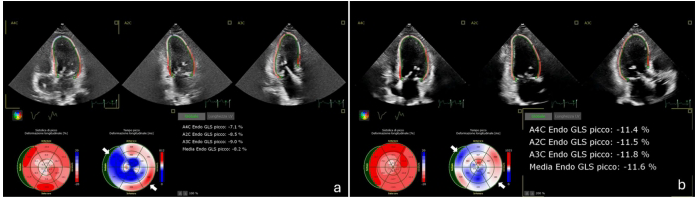

CRT的获益机制可能与纠正LBBB相关的机械不同步有关。Ezzeddine等通过二维斑点追踪成像发现,CHIC患者的LV整体纵向应变(GLS)改善幅度(-2.15%)与其他非缺血性心肌病相似,提示CRT可能通过协调心室收缩发挥作用。